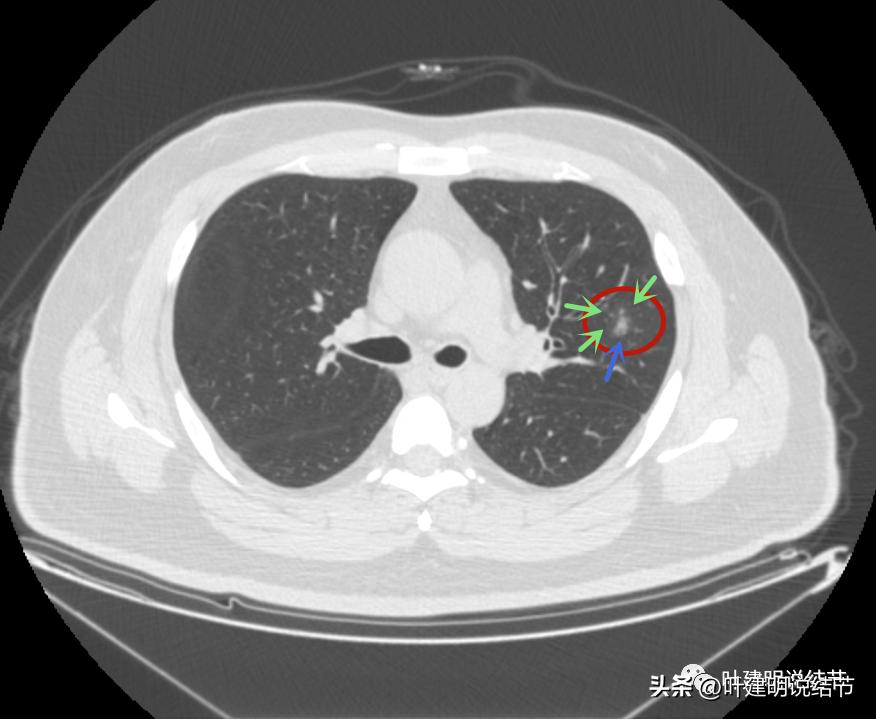

左上病灶2与左上病灶3:

病灶2出现,还只有一点点磨玻璃影,血管走行有点异样

密度略显高,有微血管进入(桔色箭头),边缘略模糊,但轮廓还是较清

中间有实性成分出现(粉色箭头),微血管进入明显(桔色箭头),边上有磨玻璃成分(绿色箭头),整体轮廓清

病灶密度不均

密度不均显杂乱

表面略不平

整体瘤肺边界与轮廓较清

边上另有病灶出现,即左上病灶3(蓝色箭头)